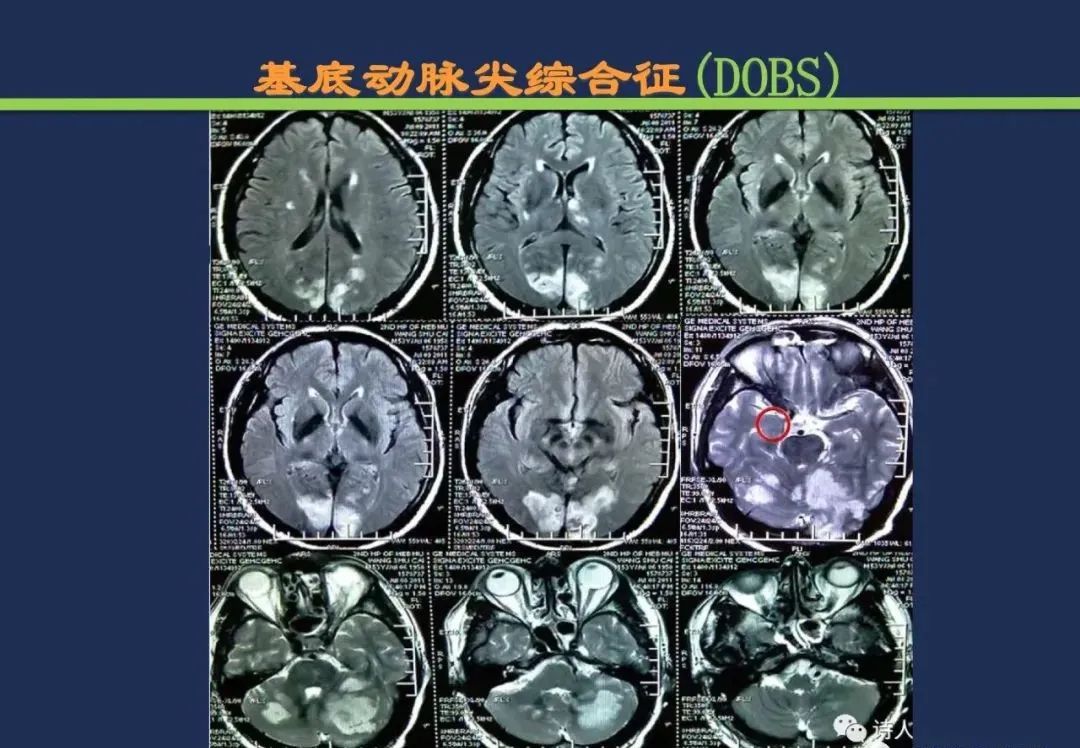

基底动脉尖